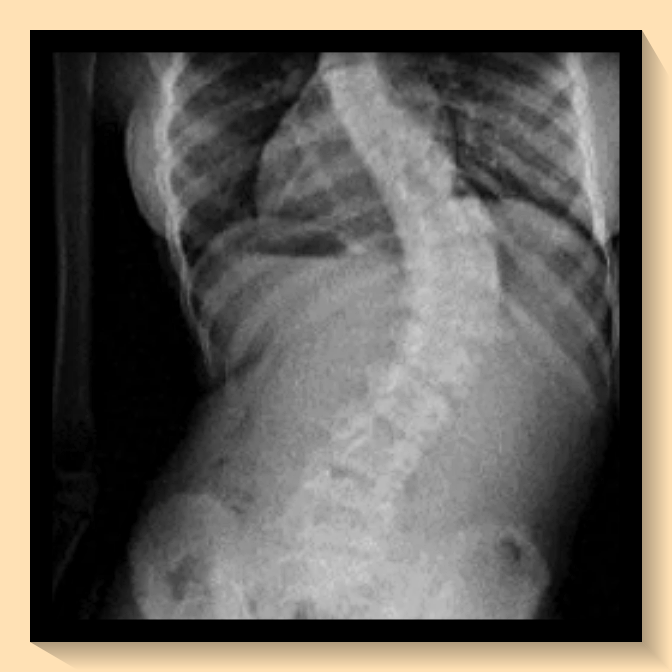

병역 신체검사에서 척추측만증의 판정을 이해하기 위해서는 '콥각도'라는 개념을 알아야 합니다. 병역 판정에 따라 등급이 달라집니다. 2024년부터는 20도 이상 40도 미만의 척추측만증 환자는 3등급으로 분류되어 현역 복무 대상이라는 새로운 기준이 적용되었습니다. 40도 이상의 경우에는 공익 판정을 받을 수 있습니다. 병무청에서는 X-ray 장비로 체크를 하지만, 병원에서 받은 서류를 준비해 가는 것이 좋습니다.

방사선 사진의 경우, CD 복사본으로 제출이 가능하며, 영상 자료 등은 비용 부담이 크다면 제출하지 않아도 무방합니다. 그러나 필요한 경우, 자료를 요구받을 수 있으니 척추측만증에 대한 정형외과 별도 기준을 확인하시는 것이 좋습니다.